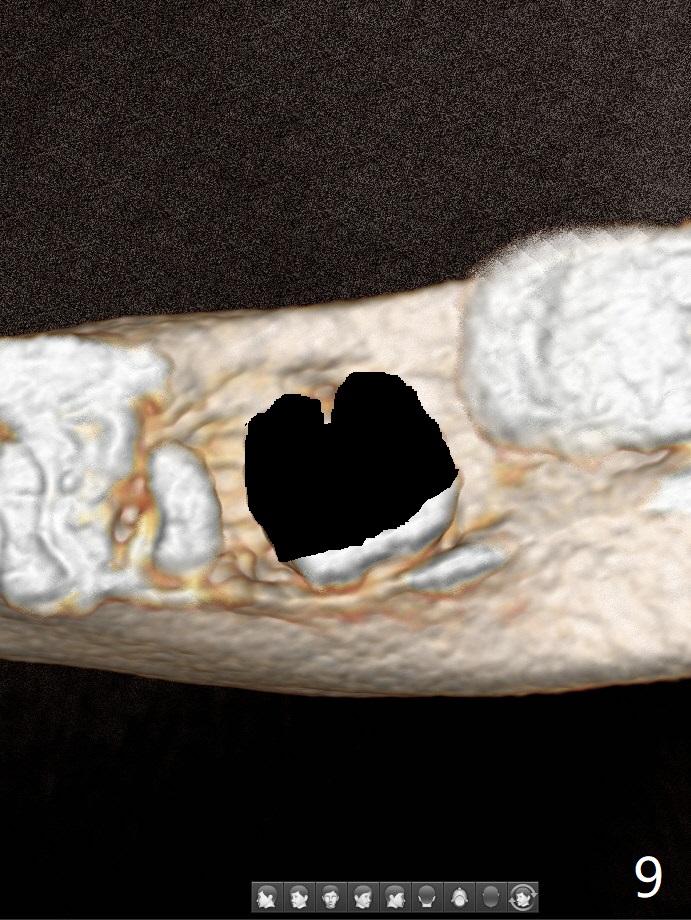

A 44-year-old woman has severe chronic periodontitis. The tooth #18 is nonsalvageable (Fig.1). To avoid distal end guide, do not remove the 3rd molar in the lab. While a 5x7.3 mm implant is long for the site (Fig.2), a 5.5x5.5 mm one seems to be a better option (Fig.3). The latter could be 1 mm more coronal. The last drill (5.0 mm) and cortical tap will be used free hand. #17 will be extracted after implantation. Since the patient is reluctant to have #16 to be extracted, place #18 implant ~ 1-2 mm more distal so that the implant crown will have some occlusal contact with #16. Prepare IS extra wide kit. Or use a 8/7 mm trephine bur to harvest cortical bone from the ramus. Drill a hole for fixation screw before removing the onlay graft. Keep the 3rd molar if possible. Prepare Tatum spacers to measure the size of #18 socket opening. In fact, the lab is able to place a 5x7.3 mm implant with 2 thread exposure buccal. Prepare sticky bone and PRFx2 to prevent periimplantitis. Soak one O-ring in case of having to extend osteotomy by .5 mm (next longer drill (1.5 mm) - 1 mm (O-ring)). For socket shield at #18 (Fig.6 *), section the tooth horizontal with a new surgical fissure bur (Fig.4 black area), use an end-cutting bur to remove buccal edge of the root (Fig.5 red area) and finally remove the lingual portion of the root (Fig.6 pink). Insert 4.5x10 mm dummy implant to determine whether the final implant 5x7.3 mm (bottom of the 1st line) will probably contact the shield. Buccal view of the lingually inclined 2nd molar (Fig.7). After removal of the crown of the 2nd molar (Fig.8 occlusal view), the lingual portion of the root is resected (Fig.9 black area). CT coronal sections show socket shield formation (Fig.10,11).

Lower Molar Immediate Implant, Prevent Molar Periimplantitis (Protocols, Table), Trajectory II, No Antibiotic Xin Wei, DDS, PhD, MS 1st edition 08/30/2019, last revision 02/02/2020